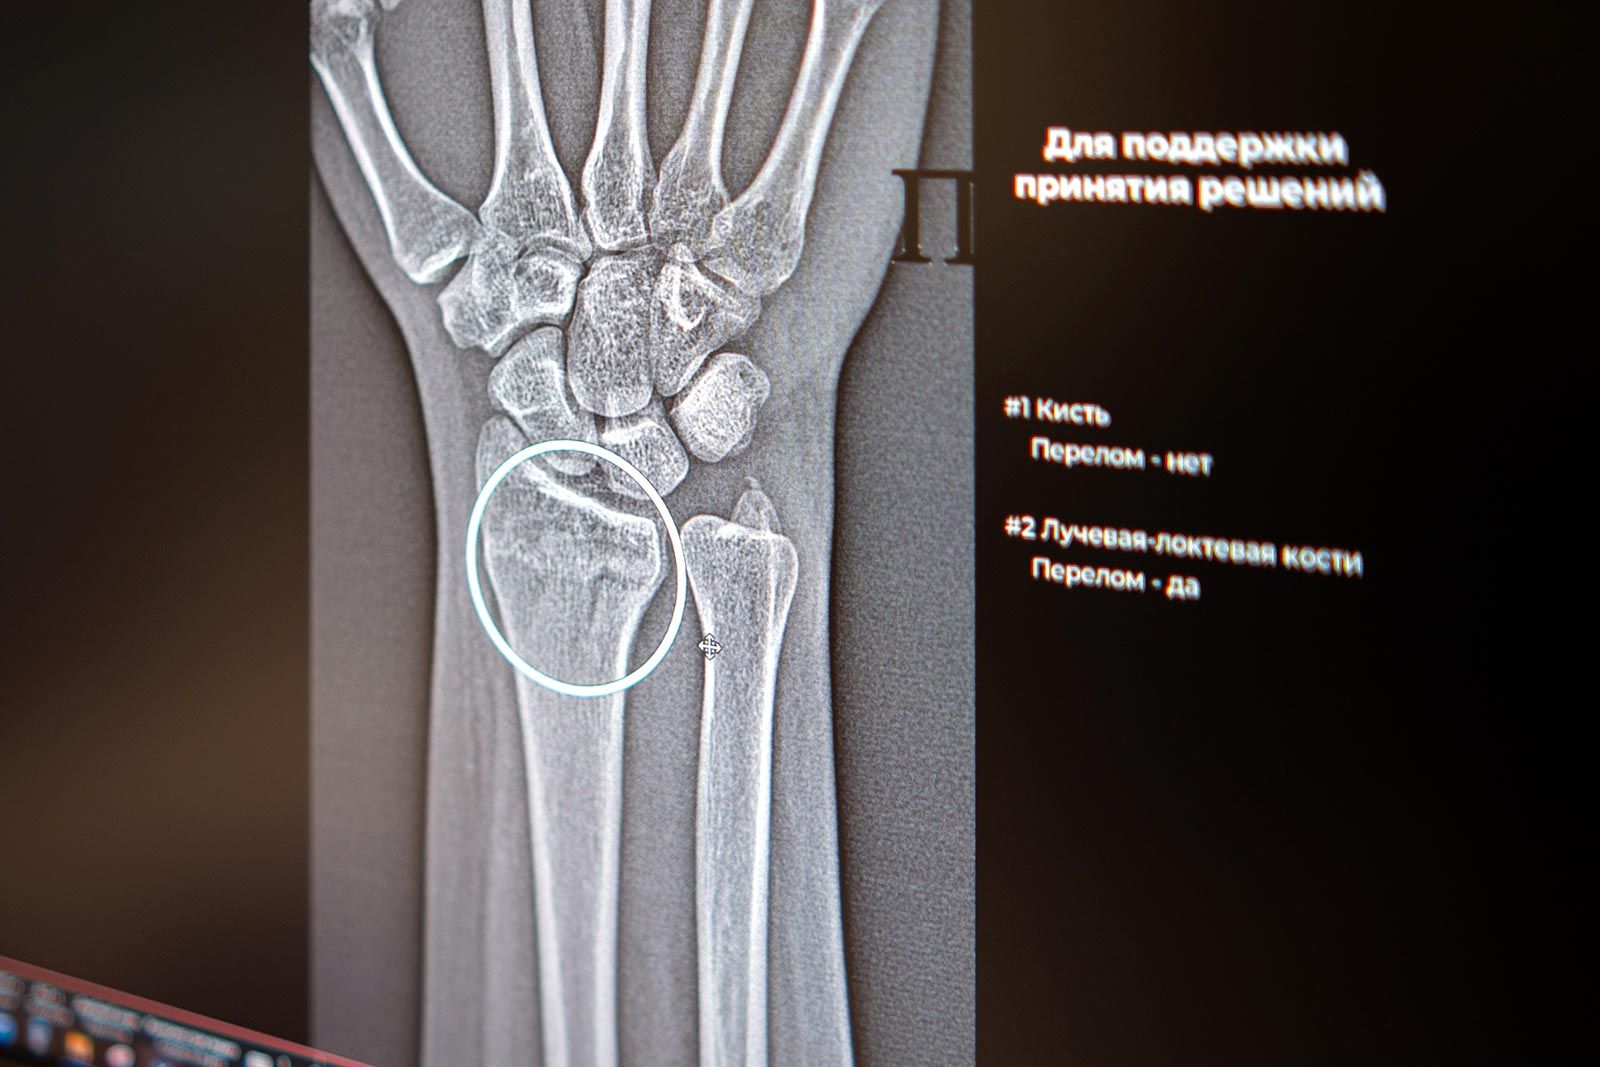

«Цифровые решения уже более пяти лет помогают столичным рентгенологам — прежде всего, в анализе медицинских снимков. Недавно мы запустили два новых ИИ-сервиса, которые помогают обнаруживать на рентгеновских изображениях травмы костей голеностопного и лучезапястного суставов — одних из самых функциональных и при этом уязвимых. Алгоритмы автоматически отметят поврежденные участки и выполнят необходимые измерения, даже если на снимке присутствуют признаки сразу нескольких переломов. Сегодня в распоряжении московских рентгенологов уже более 60 ИИ‑сервисов. Одни отличают норму от проявления заболевания, другие, например, могут измерять границы и размеры патологии. Сервисы применяются по 43 клиническим направлениям. В условиях большого потока пациентов технологичные ассистенты помогают сохранять высокое качество и скорость диагностики для каждого жителя столицы», — рассказала Анастасия Ракова.

Основными симптомами перелома являются отек и боль, которая обостряется при движении. Для минимизации негативного влияния и сохранения мобильности поврежденных суставов необходима быстрая и точная диагностика, включающая оценку масштабов травмы. ИИ-технологии в лучевой диагностике анализируют снимки по множеству параметров, помогают выполнить необходимые расчеты и позволяют ускорить описание снимка. Они могут заметить даже минимальные трещины и обратить внимание врача на то, что в этой области не один, а несколько переломов. Правильно выявленные обстоятельства позволяют выбрать подходящую тактику лечения.